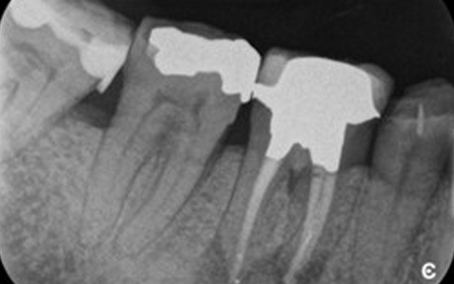

Radiograph 2 2018

Radiograph 2 2023